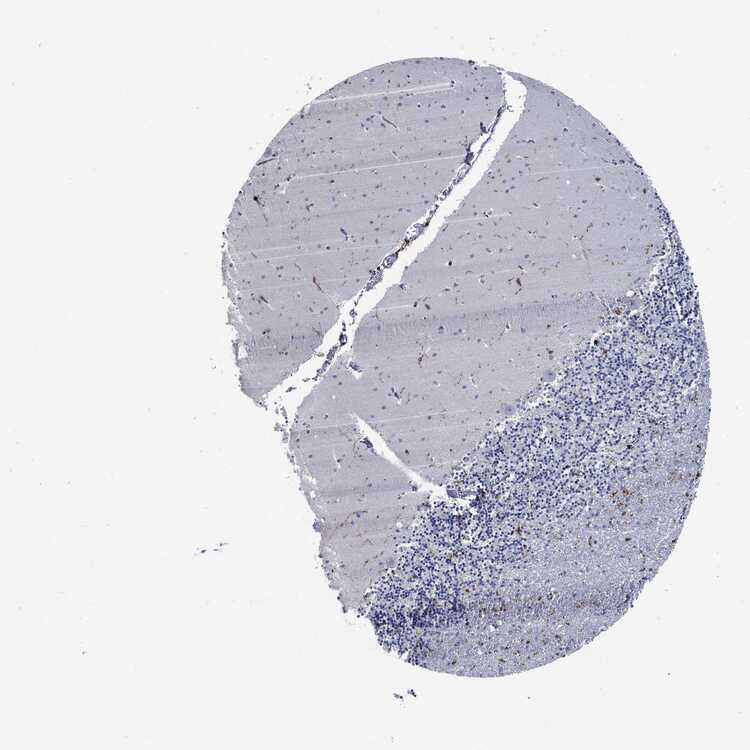

BRAIN CEREBELLUM Show tissue menu

CEREBELLUM - Expression summary

CEREBELLUM - Antibody stainingi

Antibody staining in the annotated cell types in the current human tissue is reported as not detected, low, medium, or high, based on conventional immunohistochemistry profiling in selected tissues. This score is based on the combination of the staining intensity and fraction of stained cells.

Each image is clickable and will lead to virtual microscopy that enables deeper exploration of all samples and also displays staining intensity scores, fraction scores and subcellular localization as well as patient and tissue information for each sample.

Antibody HPA000440Antibody CAB000052Antibody CAB002800Antibody CAB056154Antibody CAB068221Antibody CAB080251

Purkinje cells Not detectedNot detectedNot detectedNot detectedNot detectedNot detected

Cells in granular layer Not detectedNot detectedNot detectedNot detectedNot detectedNot detected

Cells in molecular layer Not detectedNot detectedNot detectedNot detectedNot detectedNot detected